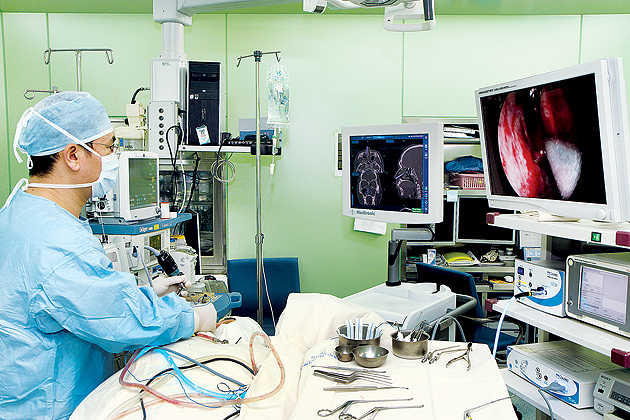

제주대학교병원 이비인후과 김정홍 교수팀이 내비게이션을 이용한 영상유도수술법을 통해 재발성 만성부비동염 환자를 수술하고 있다. 제주대학교병원

부비동염 수술.